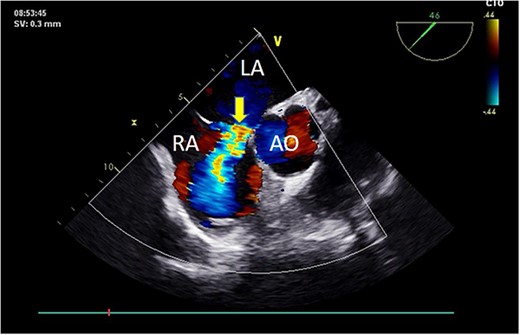

Preoperative TEE revealed moderate calcification, leaflet thickening, and hypertrophy of the tricuspid aortic valve (Fig. 1). The valve leaflets were restricted in motion, with a calculated maximum valve area of ~1.1 cm2 using the continuity equation. Color Doppler flow imaging demonstrated moderate aortic regurgitation. Additionally, a 9 mm-wide ASD was found in the mid-septal region (Fig. 2), with residual lengths on either side. Color Doppler revealed left-to-right shunting at the atrial level.

Preoperative TEE: Short-axis view reveals left-to-right atrial septal shunt with a 9 mm blood flow beam (indicated by arrow). Abbreviations: LA - left atrium; LV - left ventricle; AO - aorta.